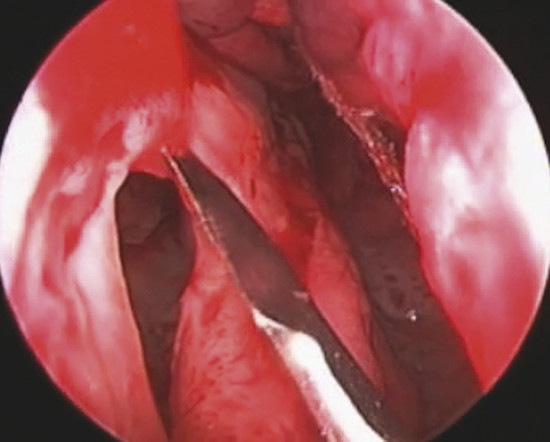

Through a hemitransfixion incision, mucoperichondrial and mucoperiosteal layers are extensively elevated on one side of the nasal septum, from the inferior edge of quadrilateral cartilage up to the choana, nasal floor, and 1 cm from the nasal roof (Fig. 19‑2).